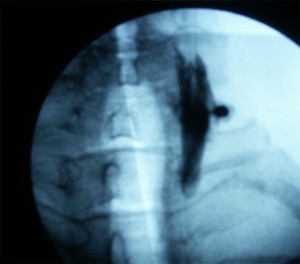

Se posiciona el arco de fluoroscopia en visión lateral y se realiza una inclinación en el plano sagital (craneocaudales) para borrar el doble contorno de las vertebras. El punto diana es la intersección de las dos bisectrices del rombo formado por el pilar superior e  inferior del mismo nivel vertebral . Se marca el punto diana con marcador en la piel por detrás o posterior al musculo esternocleidomastoideo que coincida con el punto medio del macizo articular por donde discurre el ramo medial (centro del rombo). Se introduce la aguja bajo control radiológico, evitando la dirección anterior y medial para no lesionar la arteria vertebral, la raíz y el canal espinal. Cuando se obtiene contacto óseo, se posiciona el arco de fluoroscopia en posición AP y secomprueba comprobamos la posición de las agujas que deben situarse en la concavidad del macizo facetario o valle. La lesión de debe de realizar en el nivel afectado, el superior y el inferior realizandose al menos 3 niveles. Los segmentos inferiores de difícil visualización C6 y C7 se harán en decúbito prono y de forma similar a la denervación de las facetas lumbares. Se coloca inicialmente el el arco de fluoroscopia en AP, realizamos movimientos craneocaudales para quitar el doble contorno y posteriormente inclinamos el rayo en dirección oblicua ipsilateral unos 20º hacia la zona a tratar. Se dirige la aguja en visión túnel hacia el “ojo del perrito” para localizar el nervio mediante estimulación.